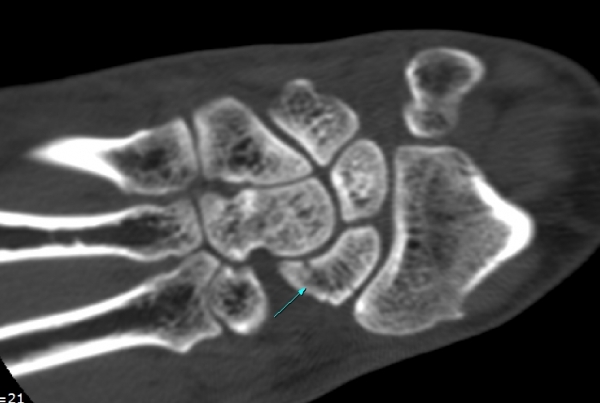

¼Õ¸ñ ÀåÃø ÁÖ»ó°ñ Á¾´Ü¸é °Ë»ç¿¡¼ ¹Ì¼¼ÇÑ ÁÖ»ó°ñ ÇÇÁú°ñ ¿¬¼Ó¼º ¼Ò½Ç(loss of cortical bone continuity)ÀÌ °üÂûµÊ(»çÁø 1, 2).

CT °Ë»ç